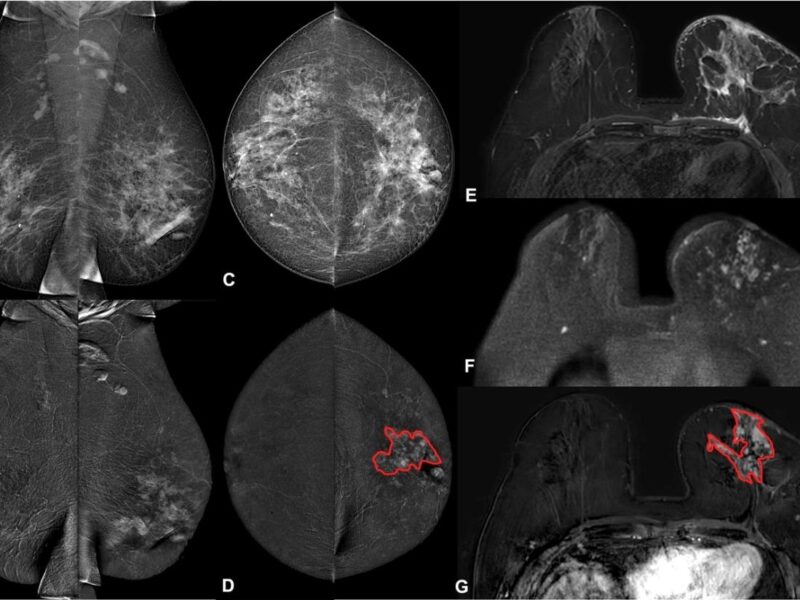

Lors d’une IRM cardiovasculaire du stress, le stress est généralement induit par injection d’adénosine ou de dobutamine. L’objectif de cette étude était de mettre au point un ergomètre d’exercice à pédale couchée à faible coût, compact et IRM compatible pour permettre de réaliser un examen de stress physique. « L’exercice physique est connu pour avoir une sensibilité plus élevée et un meilleur profil d’innocuité pour fournir un état fonctionnel et une réponse hémody